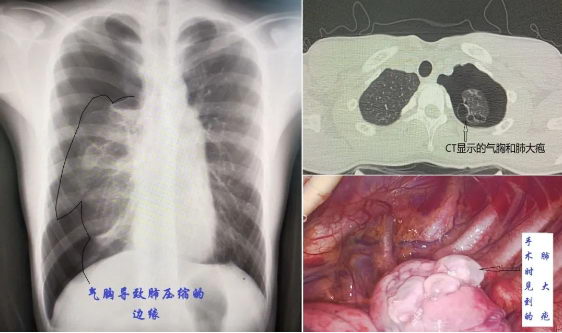

我们的肺部表面和胸壁内层之间有一层薄薄的“胸膜”,在正常情况下,两者紧密贴合,中间仅存少量润滑液体。当肺大疱破裂,空气异常地进入胸膜腔,肺部就会像被扎破的气球一样塌陷——这便是气胸,俗称“肺漏气”。

听诊+叩诊:医生使用听诊器时会发现呼吸音消失,叩诊时呈现“鼓音”。胸部X光:最常用,可见肺边缘与胸壁分离。

CT检查:更精确,能发现少量气胸或肺大疱。